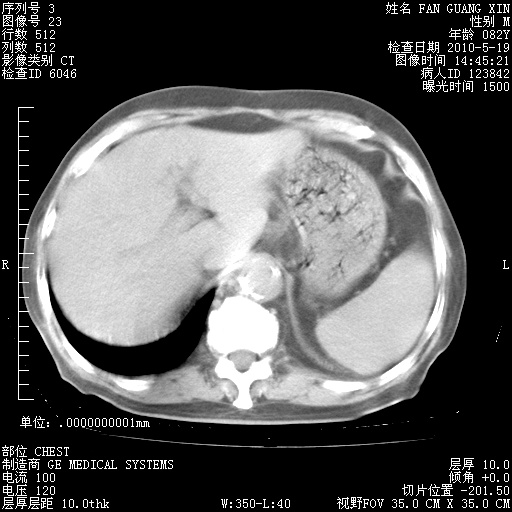

再治疗10天后的肺部CT 纵膈窗